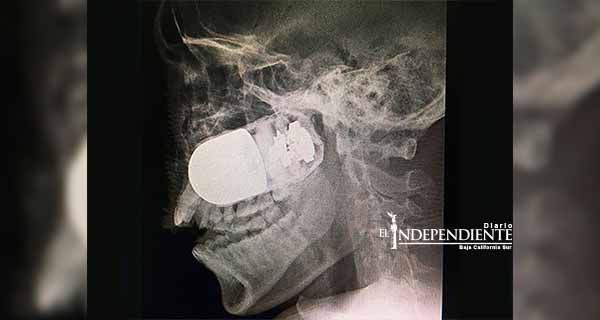

La cirugía para extraer una granada de asalto incrustada en el rostro de un soldado colombiano es un hecho excepcional y único en el mundo, porque estuvo en riesgo la vida del paciente y de todo el equipo médico del Hospital Militar Central, en esta capital.

El médico jefe de cirugías del Hospital Militar Central, William Sánchez, explicó a la prensa local que el soldado Leandro José Luna llegó el domingo pasado al centro hospitalario procedente del departamento de Arauca, en el suroccidente del país, por vía terrestre, ante la imposibilidad de trasladarlo en avión. Explicó que el soldado no podía ser trasladado vía aérea por el riesgo que explotara la granada de asalto M40, que tenía incrustada en el rostro. Por esta razón fue movilizado en una ambulancia durante un recorrido de más de ocho horas. El pasado fin de semana, el soldado estaba patrullando en las inmediaciones del río Tame, Arauca, cuando uno de sus compañeros activó en forma accidental un lanzagranadas MGL, y como consecuencia una granada se le incrustó en el rostro de Luna.

El militar “llegó en estado crítico al hospital y se tomó la decisión de atender con rapidez al paciente. El equipo quirúrgico tenía un riesgo muy elevado”, señaló Sánchez.

Insistió que este es un caso inusual, único a nivel mundial, porque se tuvo que montar todo el dispositivo médico para la cirugía en el estacionamiento a cielo abierto del Hospital Militar Central, con apoyo de expertos en explosivos para tener controlada la granada. Fue una intervención de altísimo riesgo para el paciente y el equipo médico por el alto poder explosivo que tienen las granadas de asalto, que son utilizadas en la confrontación armada que vive este país desde hace 52 años de guerra. Después de la exitosa intervención, el soldado se encuentra estable y en recuperación.